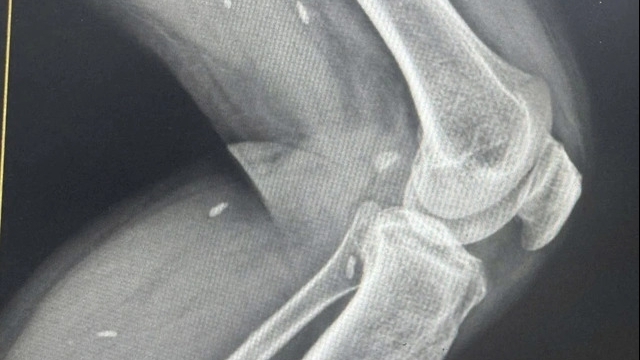

| Bé gái mắc cúm A (H5) đã cai được máy thở, cai oxy, đang theo dõi chức năng thận |

Liên quan đến bé gái bị mắc cúm A (H5), PGS.TS Tạ Anh Tuấn, Trưởng Khoa Hồi sức tích cực, Bệnh viện Nhi Trung ương cho biết: Sau 2 tuần điều trị tích cực, bé gái đã may mắn vượt qua cơn nguy kịch. Chức năng cơ quan của bệnh nhi đã hồi phục, trẻ cai được máy thở và cai oxy, tỉnh táo, chỉ còn theo dõi chức năng thận để có phác đồ điều trị phù hợp.

Được biết, trước khi khởi phát bệnh 1 tuần, gia đình bé gái có mổ gia cầm ăn, con gia cầm này nuôi cùng chuồng với đàn gia cầm bị ốm, chết.